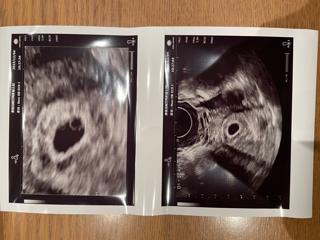

初診のエコー写真です。 この頃はまだ双子だということが判明していませんでしたが、次の検診の9w4dに先生から「2つあるから双子だね」と言われてびっくりしました。